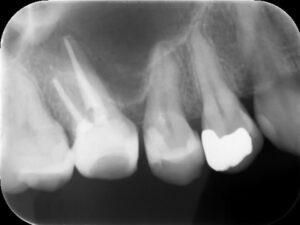

根管充填後レントゲン。症状が軽快したのでバイオセラミックシーラーとガッタパーチャにて根管充填を行った。根尖までしっかりと薬が入っているのが分かる。

治療後レントゲン。初診時の症状は完全に消失し治癒した。被せ物の適合は根管治療の予後に影響するので、しっかりとフィットする被せ物を装着することが重要。